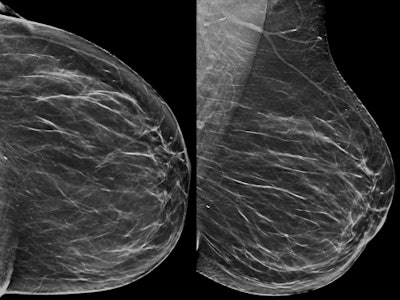

The combination of digital breast tomosynthesis (DBT) with synthesized 2D mammography images increased the cancer detection rate in an Italian breast screening program -- with recall rates and radiation dose similar to full-field digital mammography (FFDM).

As more facilities adopt DBT, many people involved in mammography have expressed the desire for a 2D image to accompany the 3D dataset. Synthesized DBT allows 2D images to be created from the 3D dataset without having to perform a second acquisition, thus reducing radiation dose.